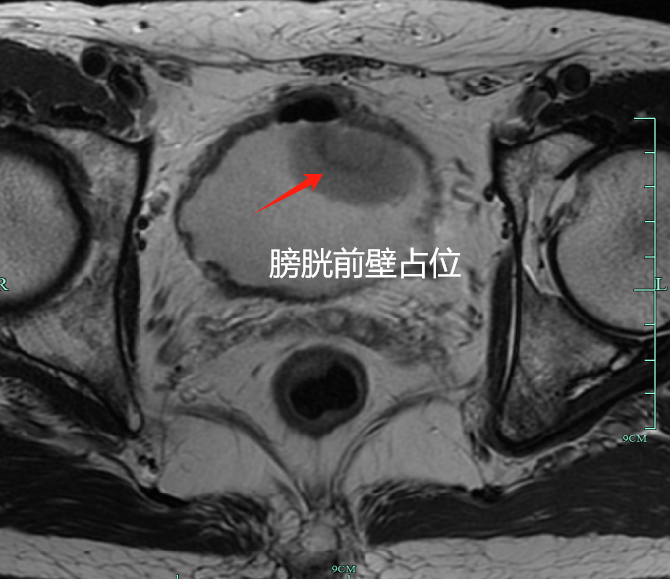

温州的亮哥经营着小工厂,生意不错。但四个月前一次上厕所,他突然发现尿液带红,当时虽然心惊了一下,但被电话打断,他也没有在意。此后血尿时有时无,颜色多变,从粉到红再到酱油色,多喝水也没改善。

因身体无明显疼痛,他迟迟没去医院。直到两个月后,他才瞒着家人到浙大一院余杭院区泌尿外科就诊。接诊医生根据膀胱镜报告,指着膀胱内肿物表示首先考虑膀胱癌,建议先做微创手术明确程度。

最终的病理提示,亮哥得的是肌层浸润性高级别尿路上皮癌,癌细胞已侵犯膀胱肌层(T2期),更具侵袭性,也更容易转移。